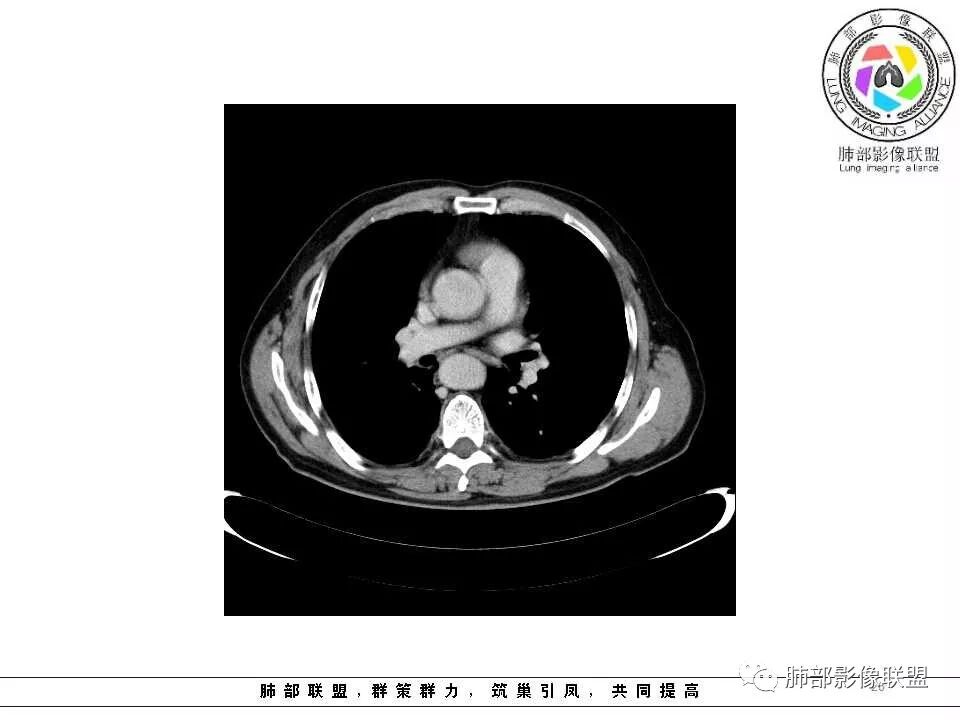

临床特点老年男性、有咯血一个月

影像学特点:肺气肿背景下在大概一年的时间里出现了一个光滑的小结节,因为图像给的不是太薄,与支气管的关系判断不清,从结节周围出现斑片状炎症来判断,应该考虑结节位于支气管内,周围是阻塞性炎症,这样比较容易解释咯血

纵隔窗上似乎结节内可见点状高密度影,同时没有明显肿大淋巴结

所以我考虑支气管内的恶性肿瘤,类癌可能大。

左肺上叶光滑结节影 似乎与支气管没有关系  ,给的纵隔窗病灶中心似乎点状钙化  病灶旁有更小结节,与上一年片比较 结节增大明显  考虑恶性 类癌可能

老年男性,肺气肿基础。约一年时间出现左肺上叶舌段支气管近端结节影,远端斑片样阴影,边缘模糊。考虑近端恶性占位,远端有阻塞性炎症。

老年男性,两肺可见小叶中央型肺气肿,提示应该有抽烟史。2016年片,右肺门支气管稍模糊,考虑慢性感染,纵膈淋巴结稍大。但2017年左肺上叶新发占位,堵塞支气管,引起局部肺不张伴感染,且纵膈淋巴结较2016年变大,患者同时伴有咯血,考虑恶性。鳞癌?类癌?小细胞?

肺气肿背景,2016年左肺上叶上舌段见微结节,2017年5月左肺结节增大,密度均匀,边缘光滑锐利,与邻近血管关系密切,血管贴壁走行,外侧见尖状突起,下舌段片状影,沿着支气管走行,内有粘液栓,考虑鳞癌,鉴别小细胞肺癌。

肺气肿背景,2016年左肺上叶上舌段见微结节,一年后左肺结节增大,密度均匀,边缘光滑、膨隆,似见小分叶,下舌段片状影,沿着支气管走行,内,老年患者,咯血1月。考虑恶性病变并阻塞性肺炎,鳞癌?注意鉴别结核。

前次片2016年4月20相应位置就有小点状病灶,2017-5-15呈结节影改变,边界膨隆,远端阻塞炎性改变,考虑肺癌,鉴别炎性结节!